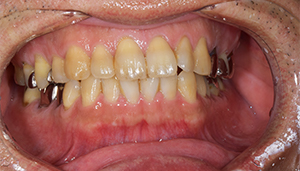

治療前:前の歯

担当医師所見:

前歯部には離開部位があり、歯頚部にはカリエスが認められる。

治療後:前の歯

前歯部はホワイトニング後に、仮歯に置き換え症状のないことを確認してからジルコニアボンドCrにて補綴。 審美性・機能面ともに調和がとれている。